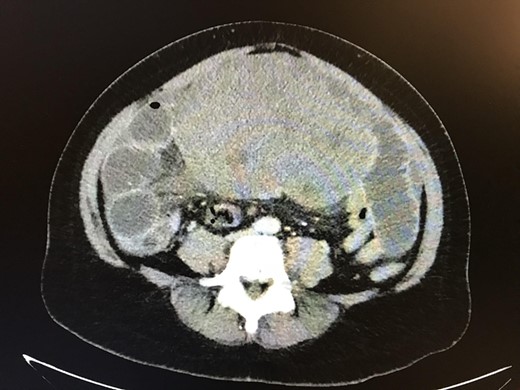

On examination, she appeared mildly distressed but with normal vital signs. Her abdomen was distended and tender to palpation in the right lower quadrant. Her hemoglobin (Hb) was 12.9 gm/dl, white blood cell count was 16 × 103/µl and platelet was 403 × 103/µl. A CT abdomen/pelvis with contrast showed a large intra-abdominal mass with resultant mechanical compression leading to a high-grade SBO (Fig. 1). Several distended loops of small bowel were noted to have thickened walls with surrounding edema raising concern for bowel ischemia.

CT abdomen/pelvis showing large intra-abdominal mass causing high-grade small bowel obstruction.